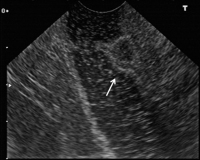

Gastrinom - Duodenum

Abbildung 4: Zirka 7 mm großes Gastrinom im Duodenum (Endosonographie).

Keywords:

Duodenum

,

Endosonographie

Gastrinom

Gastroenterologie

Vollbildansicht